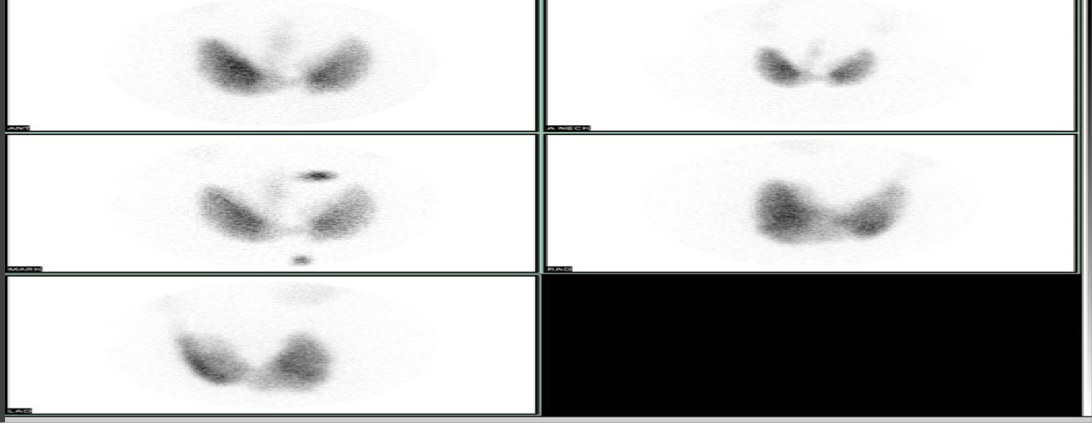

Normal lung (V/Q, ventilation and perfusion) scan

Abnormal lung scan= PE